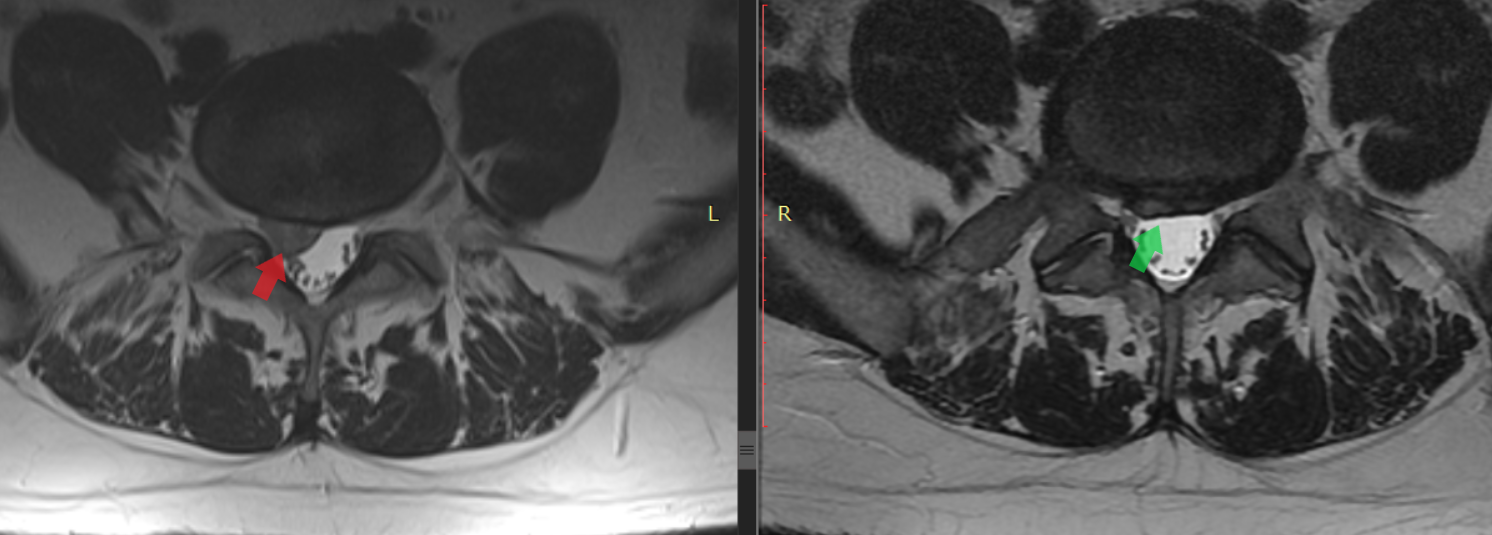

Rycina 1. Pozycycja strzałkowa. Po lewej (czerwona strzałka) przepuklina z istotnym częściowym sekwestrem L5-S1, po prawej (zielona strzałka) znaczna regresja przepukliny L5-S1 i całkowite wchłonięcie sekwestu.

Rycina 2. Przekrój poprzeczny. Po lewej (czerwona strzałka) widoczna przepuklina centralno-prawostronna z istotnym sekwestrem uciskającym struktury nerwowe. Po prawej (zielona strzałka) obraz po rehabilitacji – znaczna regresja przepukliny, swobodna przestrzeń w kanale kręgowym, brak istotnego ucisku.

Wielu pacjentów pyta: „czy każda przepuklina kręgosłupa może się sama wchłonąć?”. Odpowiedź brzmi: nie wszystkie, ale bardzo duża część – tak. Poniżej przedstawiam opis rezonansu mojego pacjenta któremu przepuklina i sekwestr uległy wchłonięciu – po lewej stronie znajduje się opis z przed rehabilitacji, a po prawej opis po rehabilitacji.